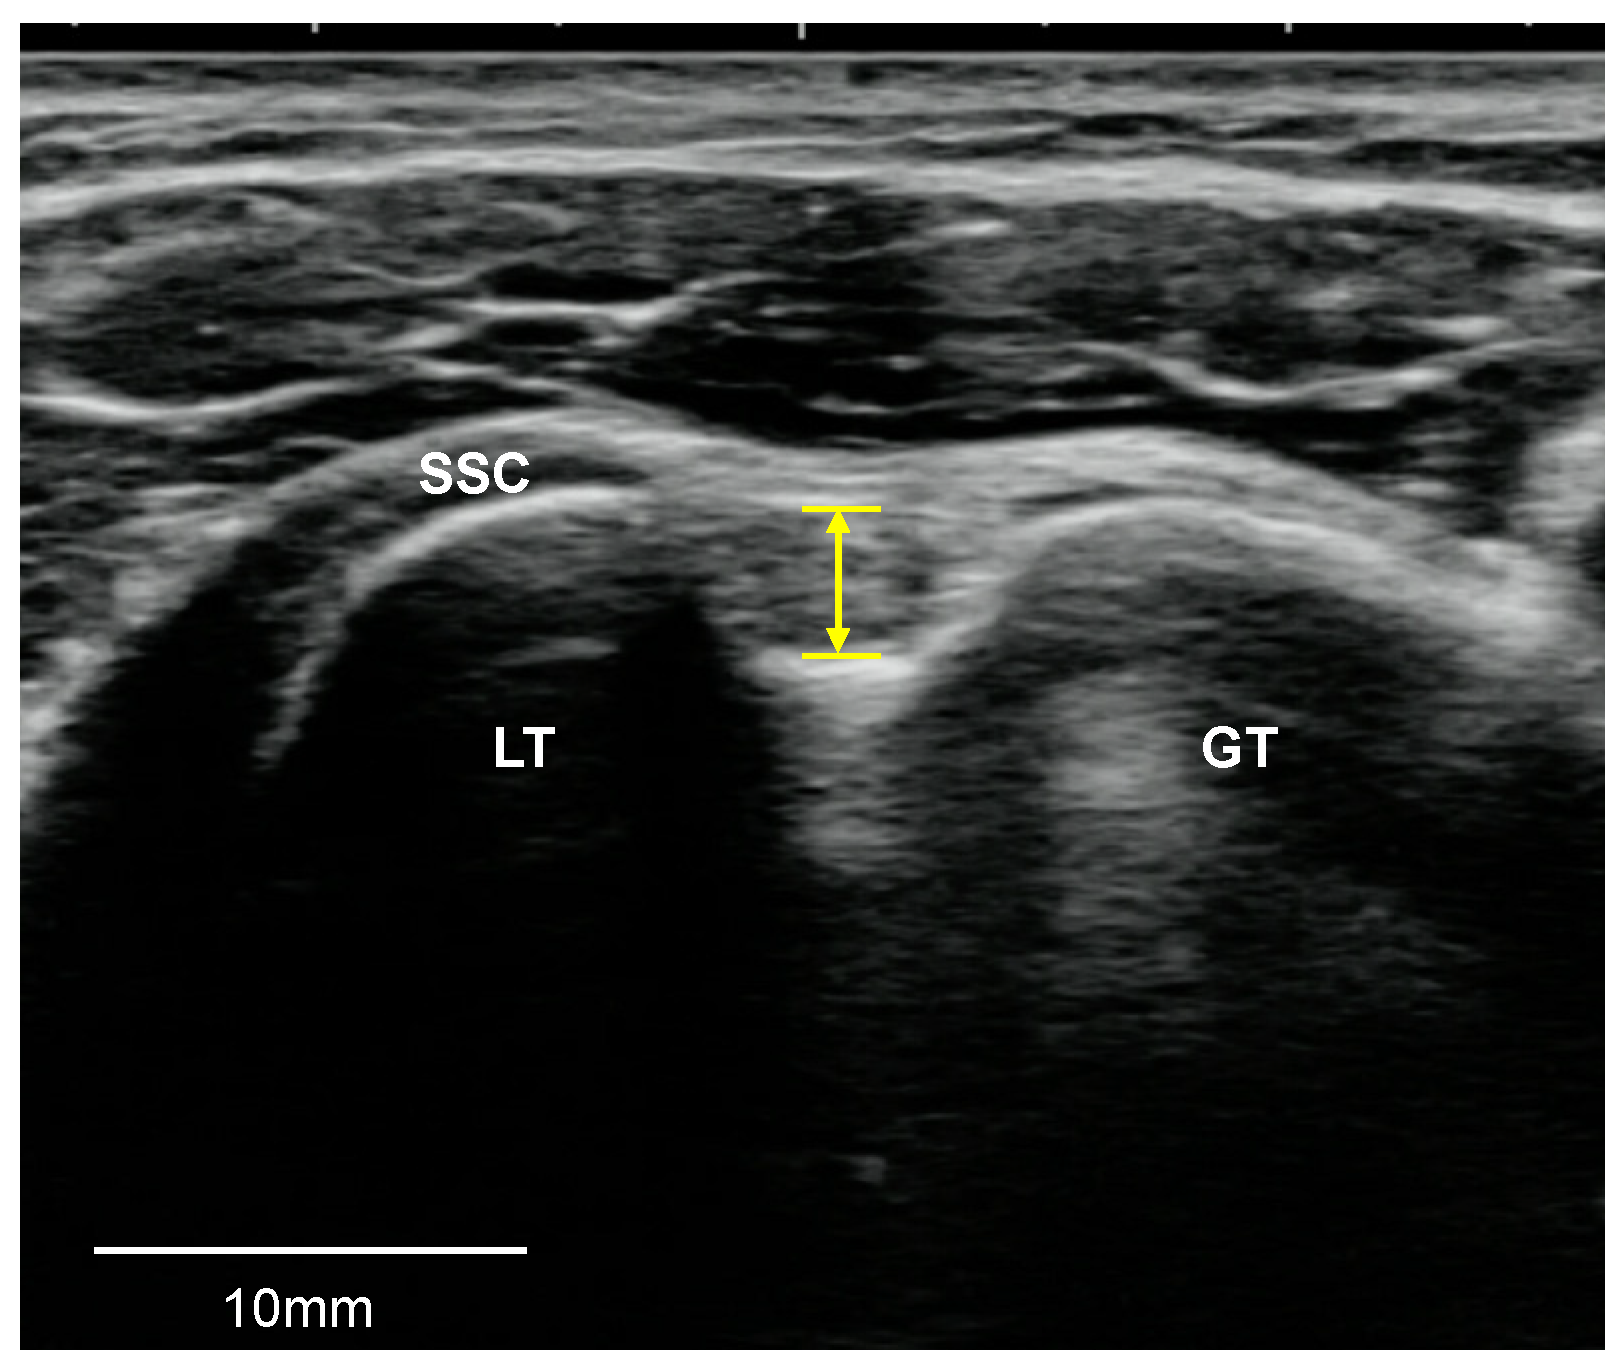

2.3.2. SSP and SSC Tendons

2.3.3. SAB